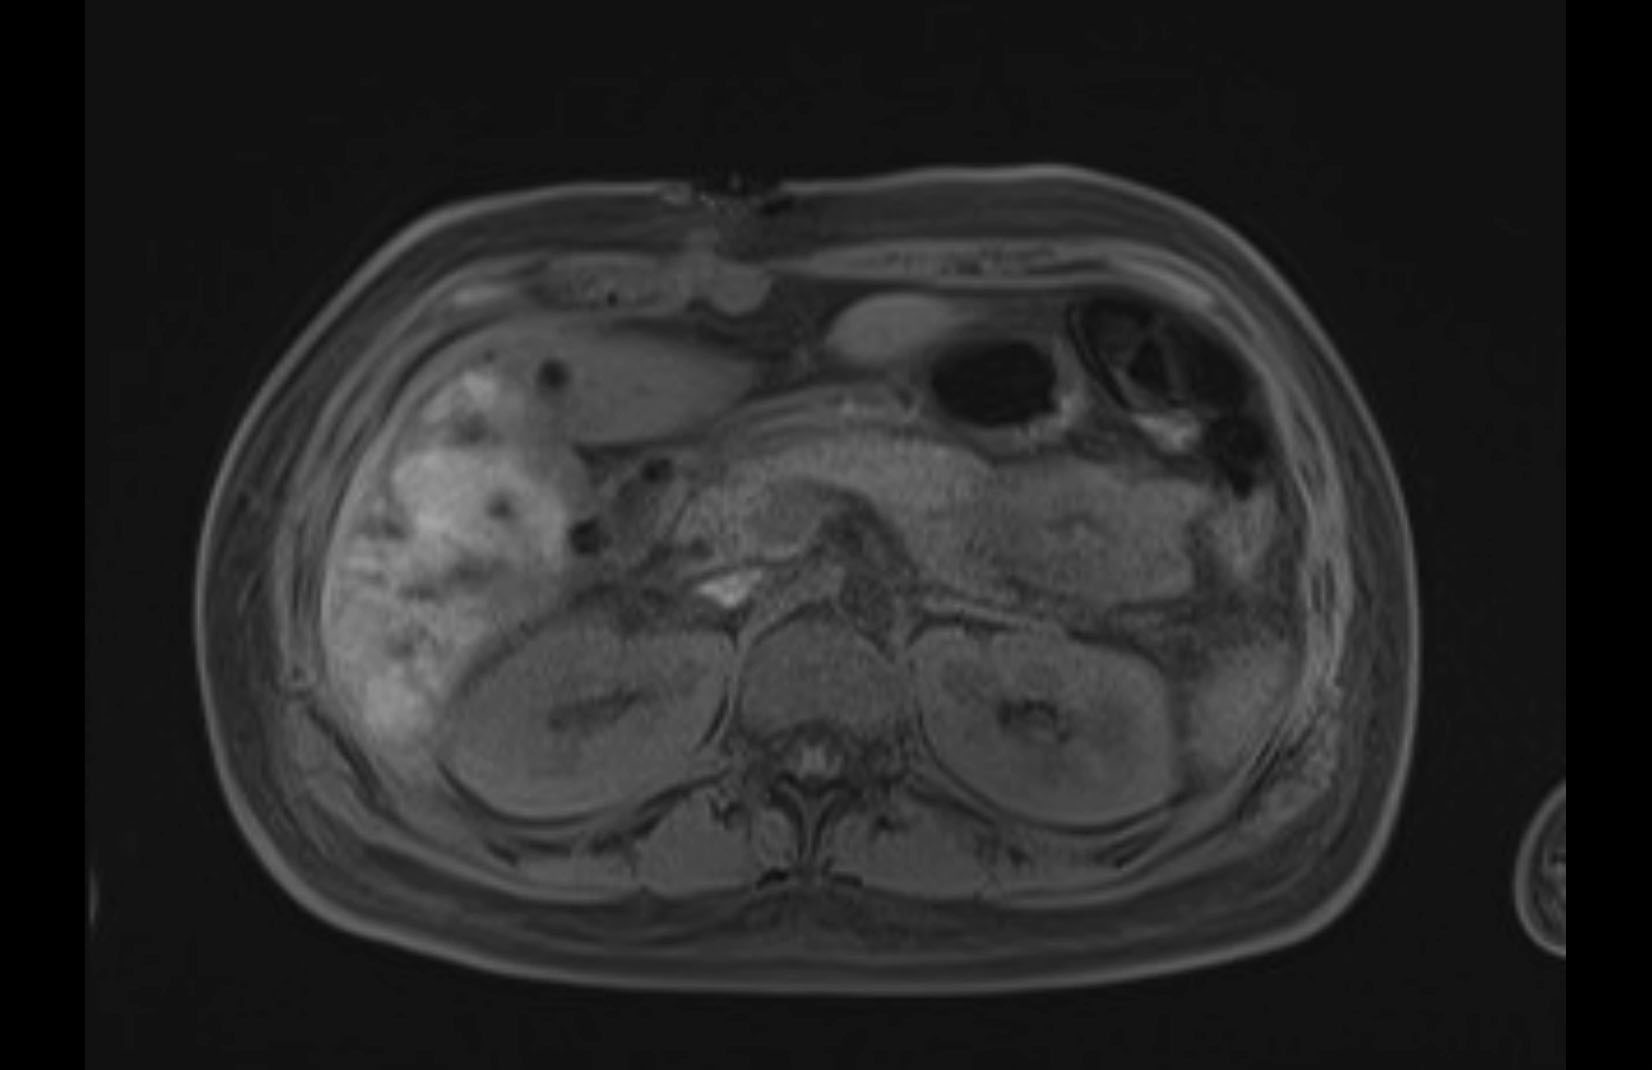

Imaging Analysis

Look through the patient's CT scan to identify any areas of concern for the necessary procedure.

MRI T1